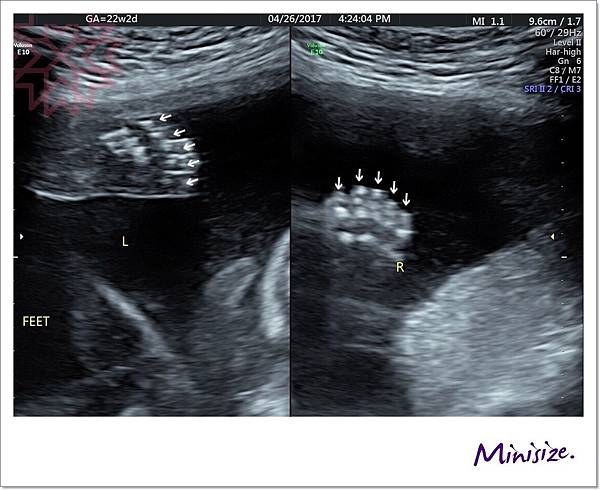

脊椎

骨骼要呈現排列整齊相互對稱

背部皮膚的表層也要光滑 完整連接

腳

腳趾就比較容易照啦

左右各是五隻腳趾頭

腳掌也發育良好